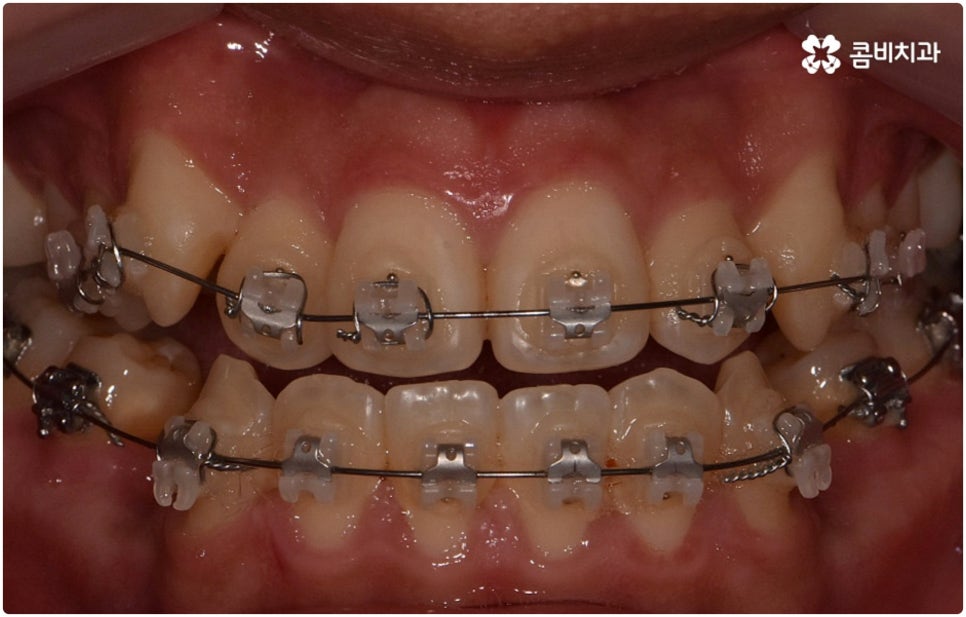

환자분들마다 상황은 모두 다르기 때문에 부정교합 교정 치료를 할 때는 정밀 검진 후 맞춤 치료 계획에 따라 무리하지 않게 진행하는 것이 중요한 포인트라고 할 수 있어요. 이때 구강내 상태 (치아, 잇몸, 치열, 교합 등) 뿐 아니라 구강 외 상태 (뼈의 위치 및 구조 발달, 얼굴 정면과 측면 등 안모 비율) 와 같은 모든 부분을 꼼꼼하게 촬영하고 환자의 연령 및 생활 습관 등을 종합적으로 고려하여 원인을 분석한 다음 치아를 어떻게 얼마나 움직여야할지 면밀하게 교정 플랜을 세우는 것이 필요하므로 3D CT, 모르페우스 같은 정밀 진단 기계를 갖추고 있는 치과에서 다양한 임상 경험을 통해 뛰어난 기술력을 가지고 있는 담당의 선생님께 치료 받으시길 권유드리고 있습니다.

하지만 관련 기술 발달로 교정에 있어서 적기라는 것이 크게 의미가 없어진 근래에는 정도가 많이 심각하지 않다면 중장년 성인분들의 경우에도 각자에게 맞는 교정 치료를 통해서 얼마든지 부정교합 개선이 가능하니 안될 것이라고 지레 짐작을 하여 내원을 망설이시기 보다는 먼저 교정 치료를 위한 검진을 받아보고 자신의 상황에 대해서 숙련된 의료진과 충분히 상담해 보시길 권유드리고 있습니다. 특히 수술적인 치료를 할 때도 교합을 바로잡기 위해서는 치과와 협진하여 진행하는 케이스가 많으니 교정을 통한 부정교합 개선 및 턱관절 치료 효과에 대해 크게 의구심을 가지실 필요는 없을 거예요. 상황에 따라 교정 치료만으로도 기능적 개선은 물론 균형잡힌 안모와 호감가는 인상으로의 변화가 가능한 경우가 많으니 불편함을 참고 계시지 말고 정밀 진단과 상담부터 차근차근 시작해 보시면 필요한 도움을 받아 보실 수 있어요.